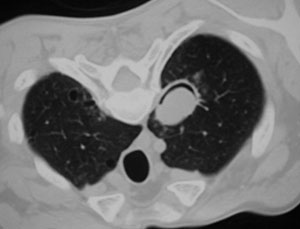

SIGNO DE LA SUELTA DE GLOBOS

La presencia de múltiples nódulos pulmonares bien definidos de distribución bilateral y aleatoria, de diferentes tamaños, es muy sugerente de metástasis pulmonares. El nombre del signo es muy gráfico.

El caso que mostramos corresponde a un paciente con metástasis de seminoma. Abajo, la imagen de TC del mismo paciente.